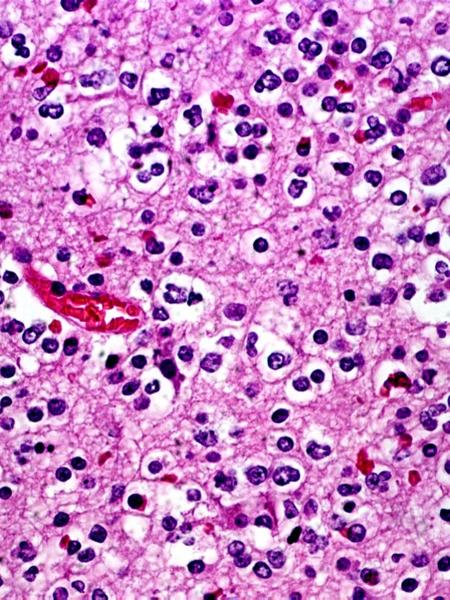

what are the haloed cells in the CNS

oligodendrocytes

what are the cells that populate this screen

why would there be clear spaces around these oligodendrocytes

just like fat (myelin) washes out from Schwann glial cells